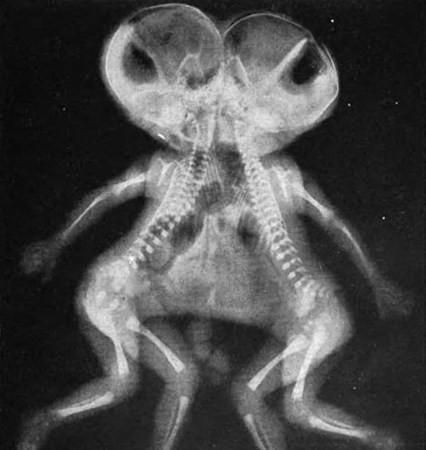

Bir röntgen sonucu neler gösterebilir? Sandığınızdan daha çok şey. Dünyanın dört bir yanından gelen röntgen görüntüleri, görenlerin ağzını açık bırakacak cinsten. Midesinden yasaklı madde çıkan mı dersiniz yoksa ayakkabı mı? Bunlar yapışık ikizlerin röntgeni. Daha ilginçleri ise sizi galerinin devamında bekliyor. İşte birbirinden ilginç ve şaşırtıcı röntgen sonuçları...

Yemek yedikten hemen sonra röntgen filmi çekilen yılan.